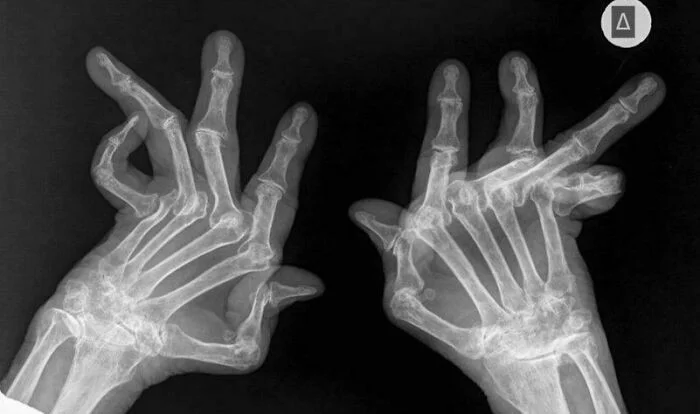

6. Как выглядит тяжелый ревматоидный артрит